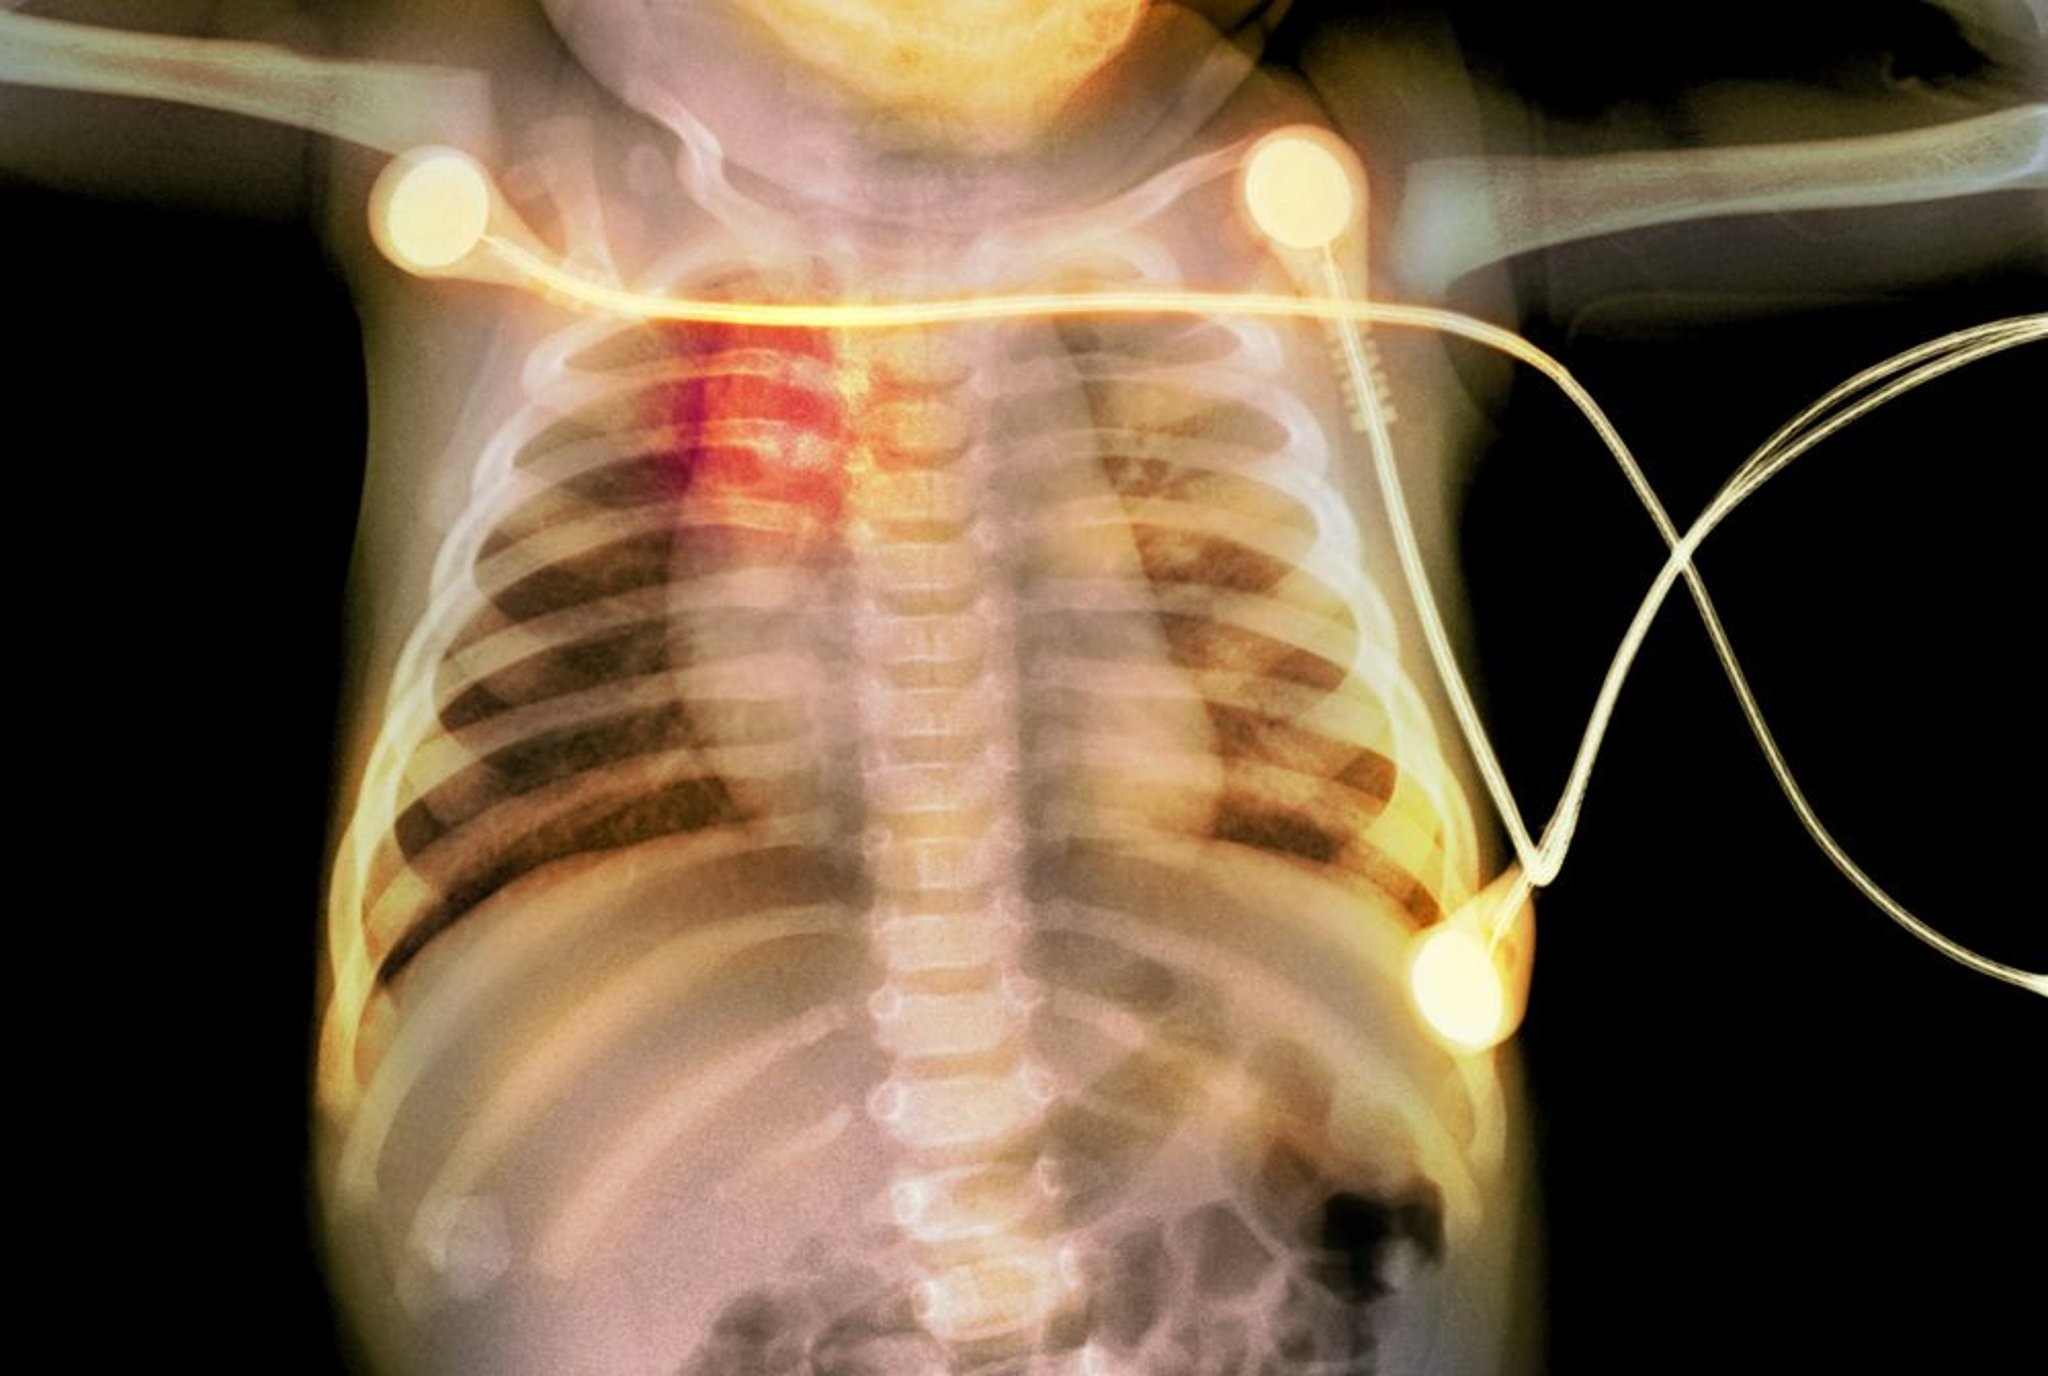

乳児の肋骨骨折

このX線写真には、乳児に生じた肋骨骨折(赤色でハイライトされた部分)が写っています。これは小児虐待を示唆するものです。